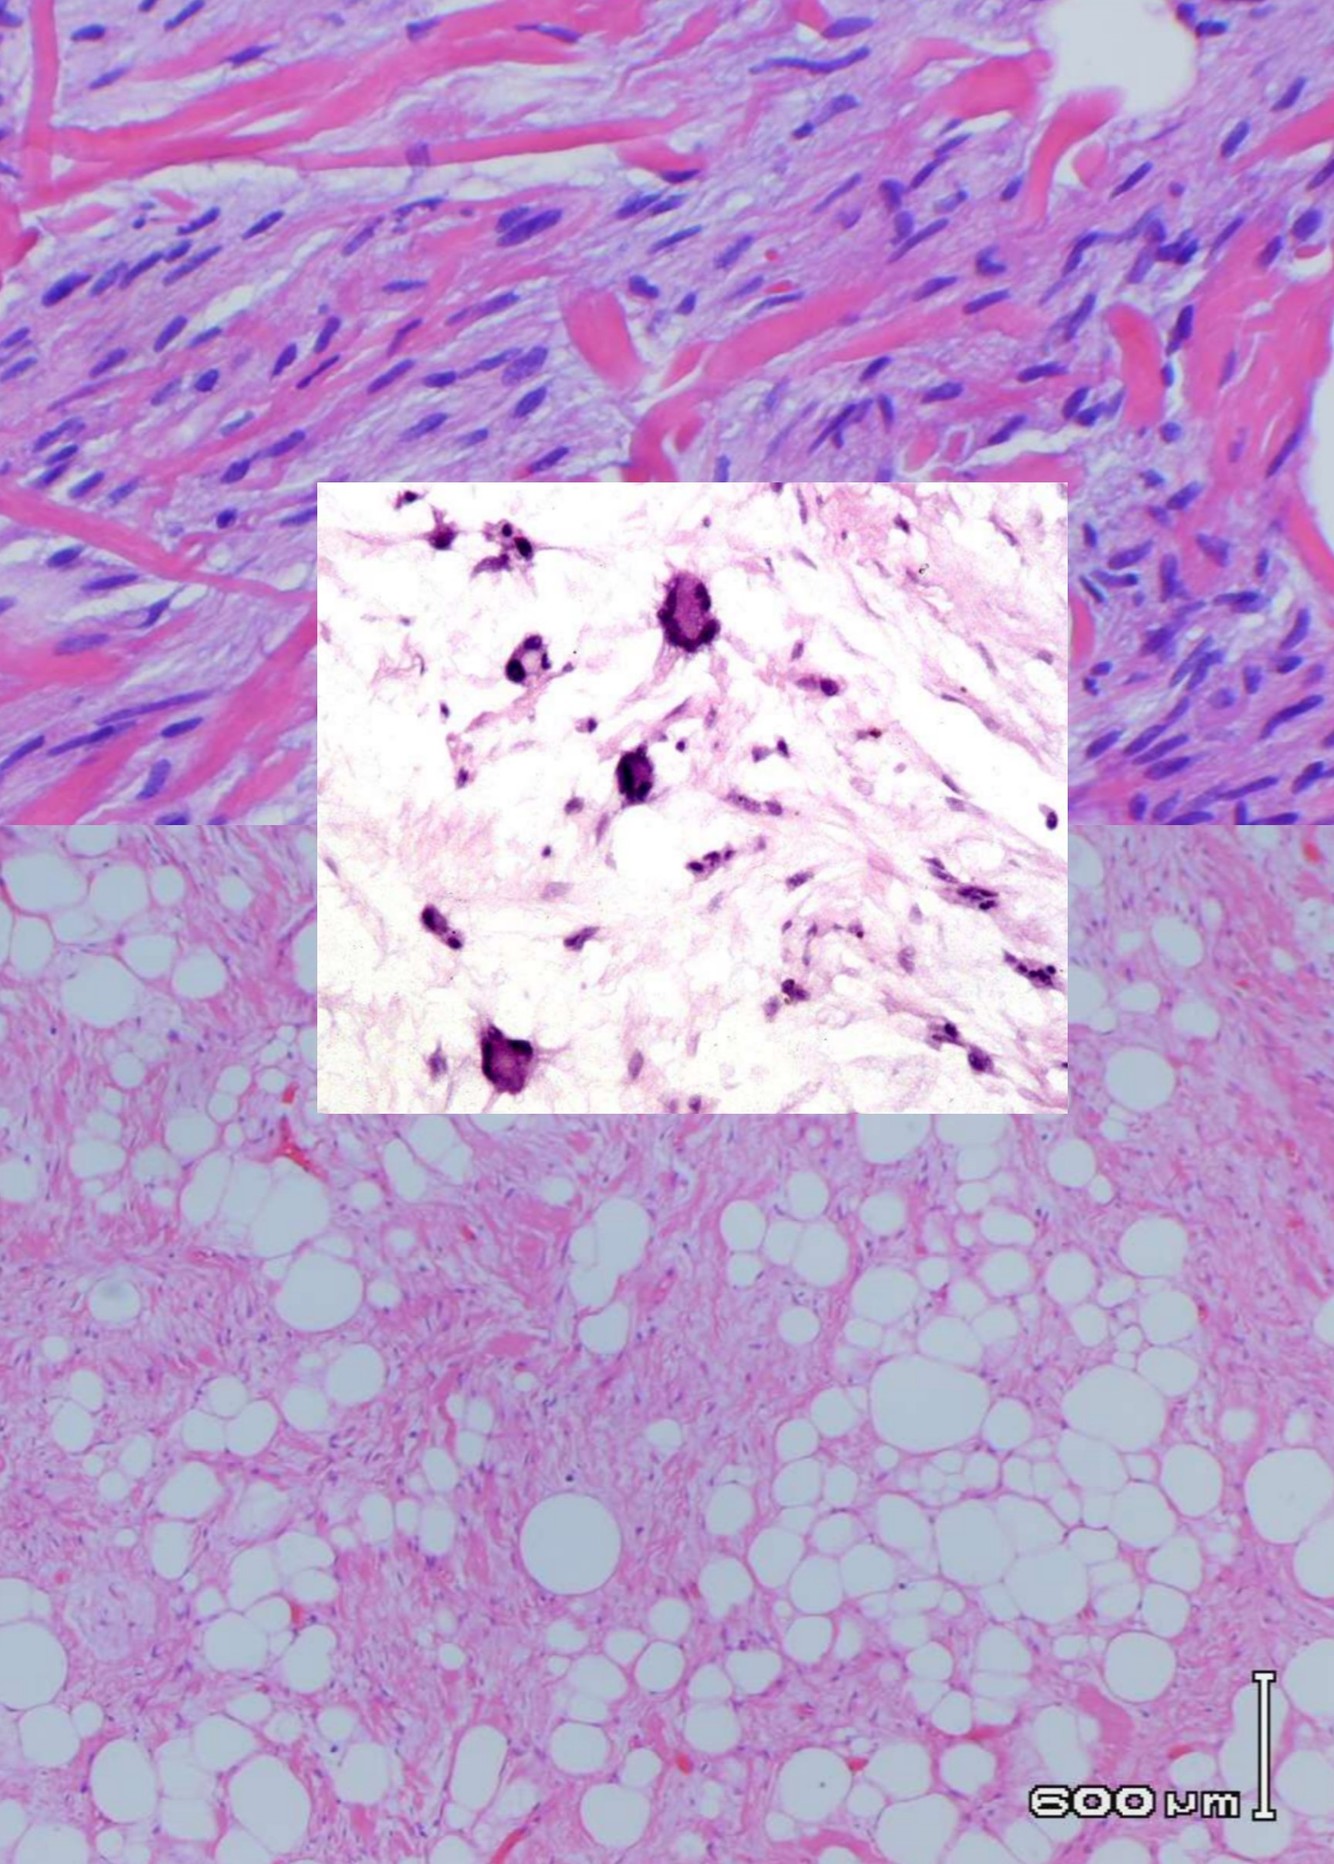

SPINDLE CELL LIPOMA

• Subcutaneous mass, posterior neck, shoulder and upper back

• Similar tumors elsewhere classified as atypical lipomatous tumors or well differentiated liposarcoma if deep

• Men 90%, 45-65 yo

• Genetics:

• 16q or 13q abnormalities in 70%

• Frequently hypodiploid

• Gross:

• Usually 3-5 cm, well circumscribed, yellow-gray-white, firmer than classic lipoma

• Histology:

• Mature adipose tissue, spindled cells, and ropy collagen

• Floret-like multinucleated giant cells –> pleomorphic lipoma

• CD 34+